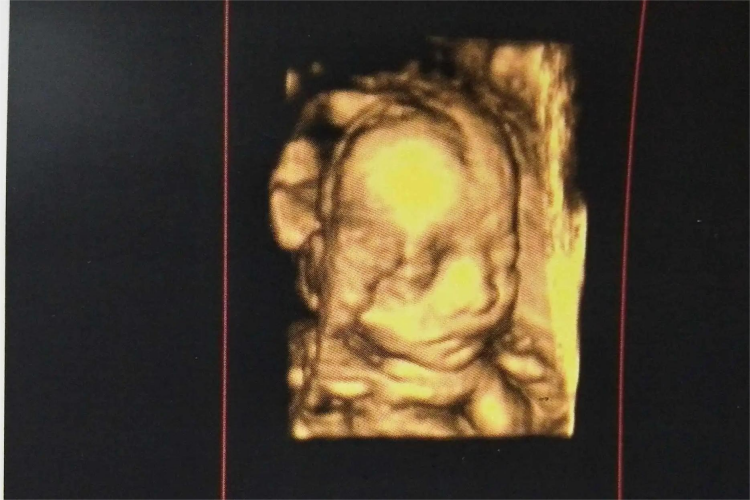

5个月胎儿,即孕20周左右,属于妊娠中期,彩超下可见胎儿身长约25cm,顶臀长16cm;皮肤暗红,出现胎脂,全身覆盖毳毛,可见少许头发。在胎儿5-6个月,可采用超声进行胎儿系统检查,筛查胎儿结构畸形。5个月胎儿增长速度较快,开始出现吞咽、排尿功能;自该孕周起胎儿体重呈线性增长;胎儿运动明显增加,10%-30%时间胎动活跃。